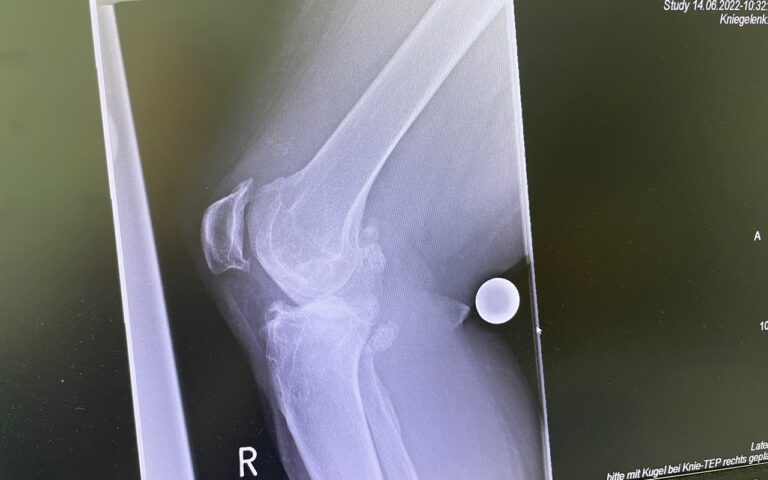

Η ολική αρθροπλαστική γόνατος είναι χειρουργική επέμβαση κατά την οποία αντικαθίσταται η φθαρμένη άρθρωση του γόνατος με τεχνητά εμφυτεύματα.

Στόχος είναι η ανακούφιση από τον πόνο, η βελτίωση της κίνησης και η αποκατάσταση της λειτουργικότητας του γόνατος.

Πώς γίνεται η επέμβαση

Κατά την ολική αρθροπλαστική:

• αφαιρούνται οι φθαρμένες αρθρικές επιφάνειες

• τοποθετούνται μεταλλικά εμφυτεύματα στο μηριαίο οστό και την κνήμη

• παρεμβάλλεται ειδικό ένθετο πολυαιθυλενίου

• σε επιλεγμένες περιπτώσεις αντικαθίσταται και η επιγονατίδα

Τεχνική & εξατομίκευση

Η επιλογή της τεχνικής και της πρόθεσης γίνεται εξατομικευμένα, λαμβάνοντας υπόψη:

Στόχος είναι η σωστή ευθυγράμμιση, η σταθερότητα και το φυσικό εύρος κίνησης.